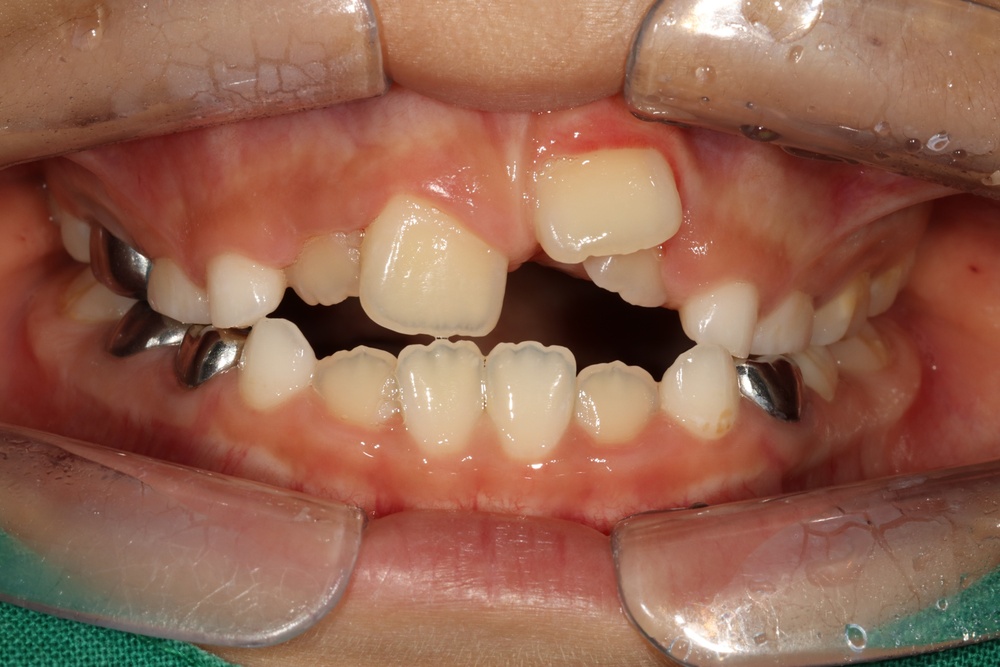

40대의 환자분으로, 앞니가 비뚤어서 코로나가 끝났을 때 마스크를 벗고 웃고 싶다고 하셨습니다.

충치가 많아서 교정 전 충치치료를 전반적으로 시행하고, 잇몸치료도 진행하였습니다.

중년기 교정에서 발생가능한 문제점(치아 사이 틈 발생가능성, 잇몸질환)충분히 설명드리고 시작하였습니다.

치아 배열이 거의 완성된 상태로 치료 전 말씀드렸던 치아사이의 틈(블랙트라이앵글)이 있습니다.